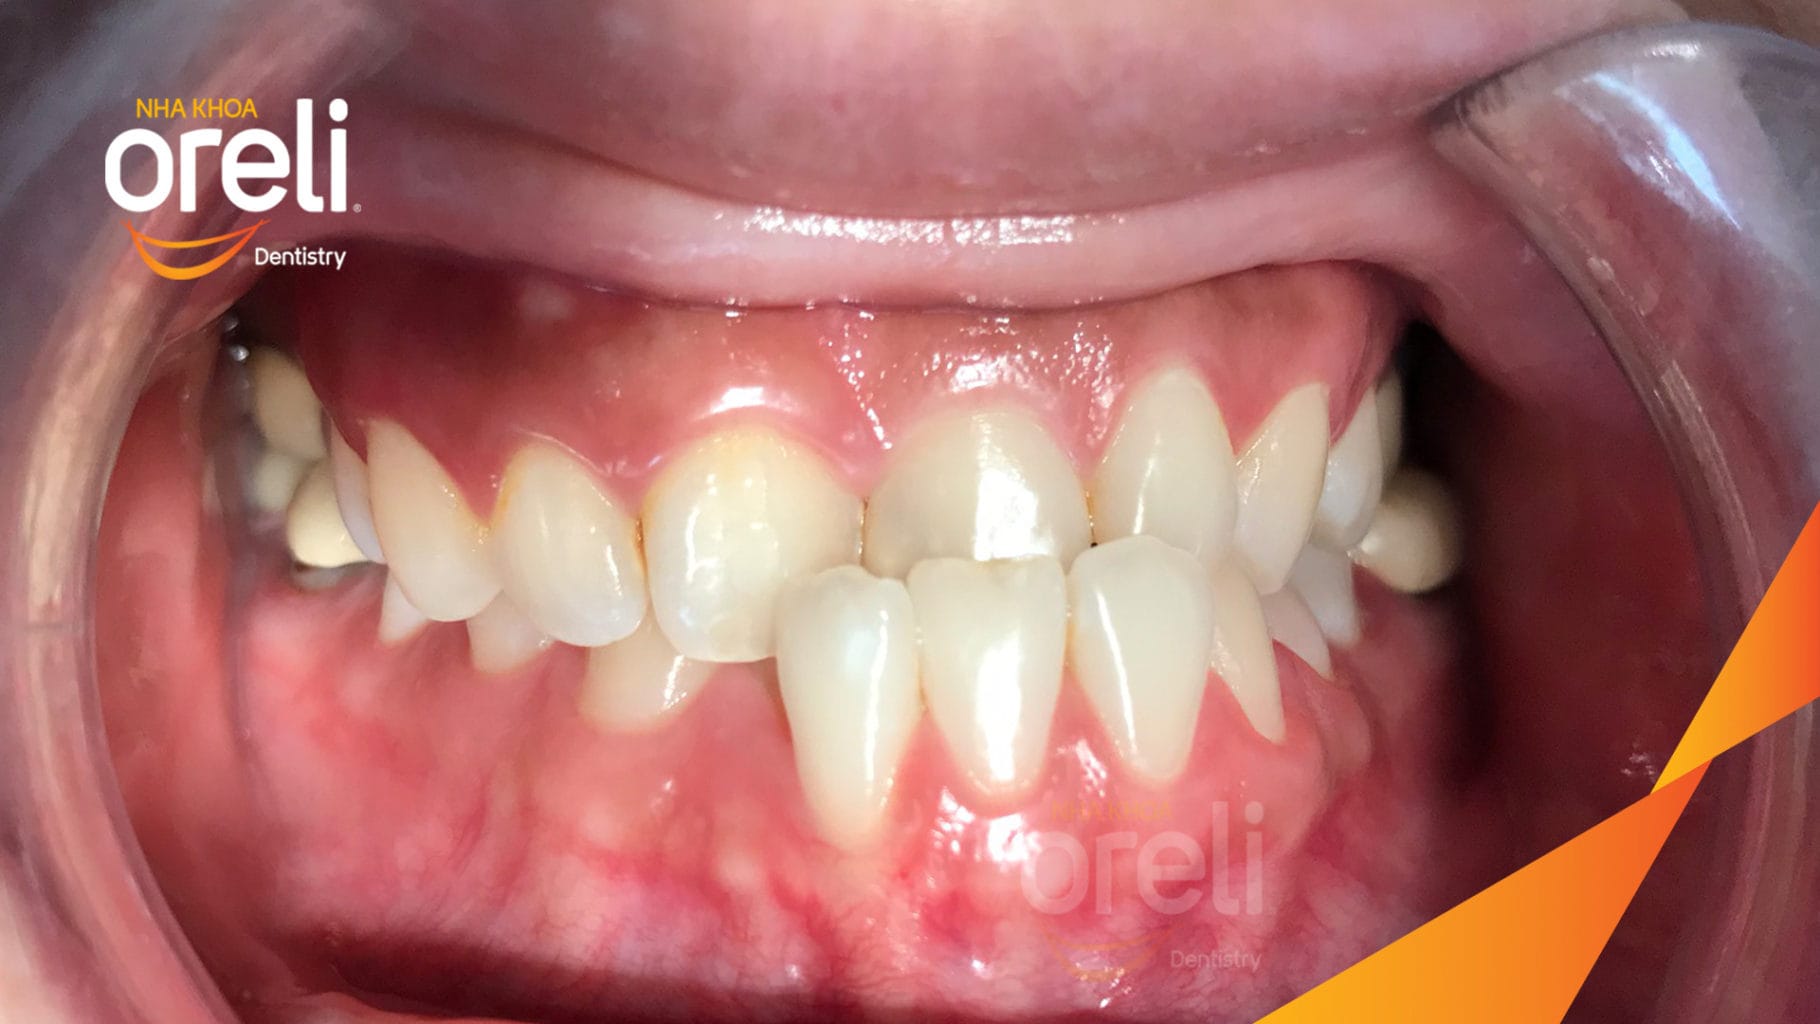

Ca niềng hạng 3 móm di gần răng 78 cho nụ cười đẹp ở Oreli

Ca niềng răng di gần răng 7 8 phục hồi ăn nhai và thẩm mỹ nụ cười. Kết quả thực tế trước và sau điều trị tại Nha khoa Oreli.